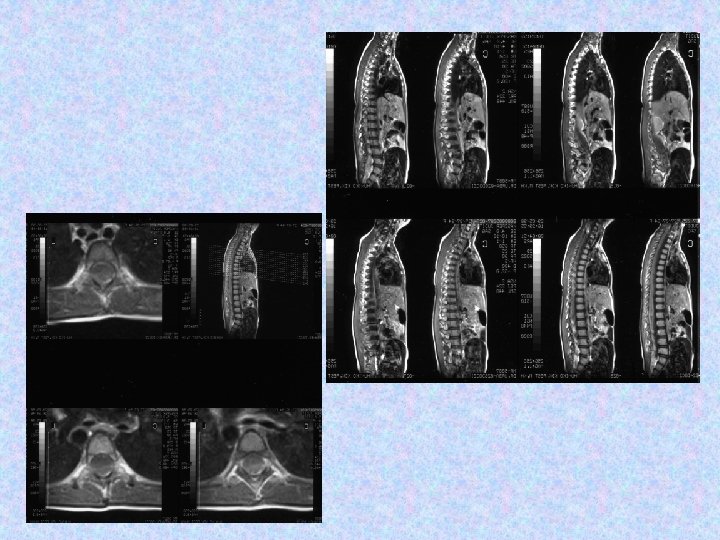

• A 2006. szeptember 27 -i MRI összevetve a 2005. november 16 -i MRI-vel: a halmozás amorf formájú növekvő tumor masszát mutat mindkét frontális kamraszarvban. A kamrarendszer továbbra is tág. A caudalis durazsák halmozó tumor masszával kitöltött.

• A következő műtét 2006. októberében történt. Részleges eltávolítás, aqueductoplasica történt. Szövettan pilocitás asztrocitómát igazolt. • 2006. 12. 16 -án készült MR vizsgálat kiterjedt intraventriculáris, subarachnoideális, thoracolumbális halmozási többletekkel járó teljes neuraxist érintő disszeminációt ábrázolt.

• Progrediáló járászavar, bal oldali alsóvégtagi fájdalom miatt megismételt MR vizsgálat L. I. szintben igazolt myeloncompressiót okozó növekedést az egyebekben változatlan szóródás mellett. 2007. 01. 19 -i műtét során parciális eltávolítás történt, objektivizált teljes tumorszóródás mellett.